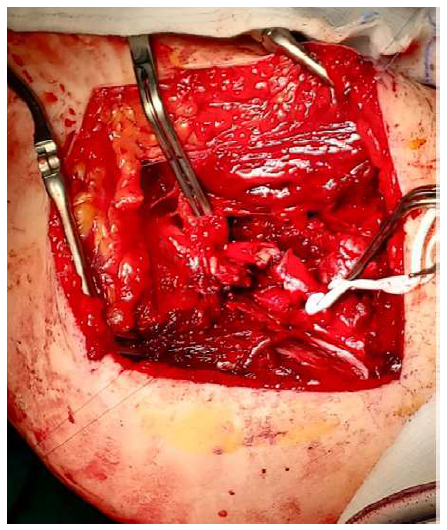

Considering the emergency, the patient was immediately transferred to the operating room. Surgical exposure revealed an approximately 20-cm-wide total resection of muscle and subcutaneous tissue in the thigh area. The SFA was severed (Figure 1) and presented severe atheroma with multiple and irregular calcifications. Additionally, the SFV’s anterior wall was disrupted and associated with local thrombosis. The injured SFA segment (4-5 cm) was resected, the third proximal segment of the right great saphenous vein (GSV) was isolated and prepared, and a GSV to SFA interposition bypass was performed (Figure 2). The SFV was ligated.

Figure 1 Intraoperative image of the surgical exposure prior to revascularization. The superficial femoral artery and vein are visualised, exhibiting traumatic injuries.